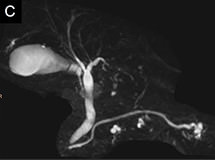

図1 MRIによるMRCP画像

胆嚢、胆管、膵管の3次元画像が造影剤を使用せずに撮像可能です。

• A.胆管癌

• B.肝内胆管癌

• C.膵臓の嚢胞性腫瘍